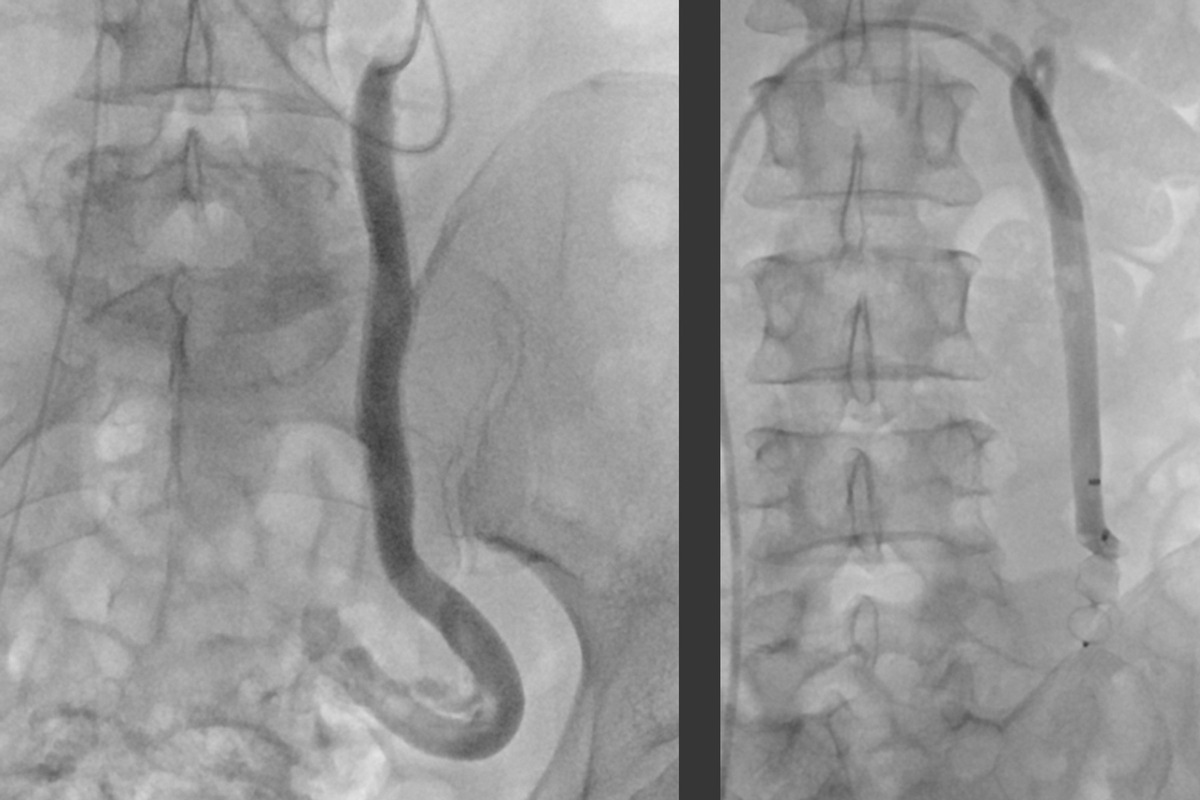

Bei der Embolisation wird ein dünner Katheter über die Leiste (selten auch über einen Zugang am Arm oder Hals) in die Vene eingeführt. Unter Röntgenkontrolle und Kontrastmittelgabe wird dieser Katheter zu den erweiterten Beckenvenen vorgeschoben. Die betroffenen Venen werden nun gezielt von innen verödet und anschließend mit kleinen Spiralen oder speziellen „Stöpseln“ über den Katheter verschlossen. Dadurch wird der krankhafte Rückfluss des Blutes unterbrochen. Der venöse Abfluss erfolgt danach problemlose über gesunde Umgehungswege.